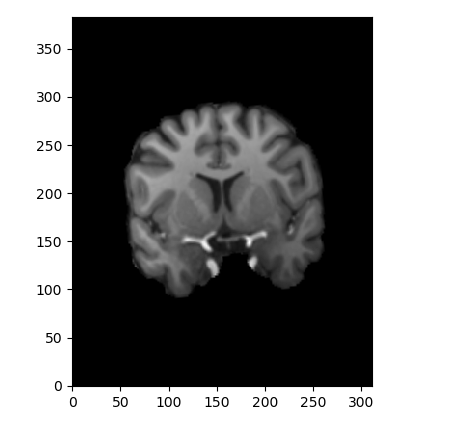

我试着用另一个病人的脑部MRI作为参考,并以不同的角度进行检查。在这里,从这个核磁共振切片(所有的文件都是nifti格式):

现在,魔法已经发生了。将第一个MRI作为注册工具的输入,最后这个MRI作为参考MRI

结果是,注册工具(Flirt)的输出是一个MRI,其中切片具有这样的角度: